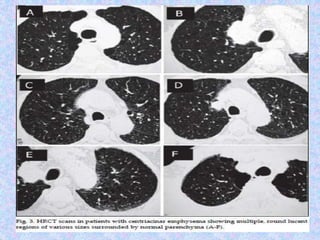

CT finding in emphysema is diagnosed by alveolar septal destruction and

airspace enlargement, which may occur in a variety of distributions.

Centrilobular emphysema is predominantly seen in the upper lobes with

panlobular emphysema predominating in the lower lobes. Paraseptal

emphysema tends to occur near lung fissures and pleura. Formation of giant

bullae may lead to compression of mediastinal structures, while rupture of

pleural blebs may produce spontaneous pneumothorax /

pneumomediastinum.